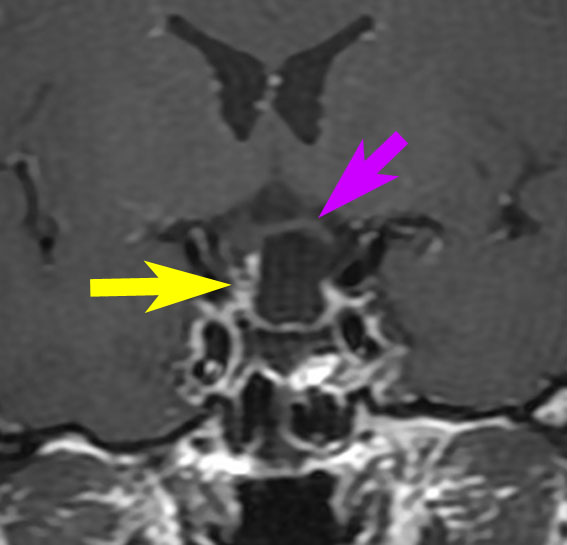

左は下垂体腺腫(緑の腫瘍)が内頚動脈に挟まれていることを示しています。

中央は手術前の下垂体腺腫で,視神経も正常下垂体も位置はわかりません。

右は手術翌日の画像です。黄色の矢印の先が残した正常下垂体組織です。桃色の矢印の先に視神経(視交叉)がはっきり見えています。術後の一時的な尿崩症がありました。クモ膜が残っているので髄液漏は生じませんでした。でも正常下垂体組織(黄色矢印)も視交叉も腫瘍に圧迫されてペラペラになっていますから,いつもうまく行くとは限りません。